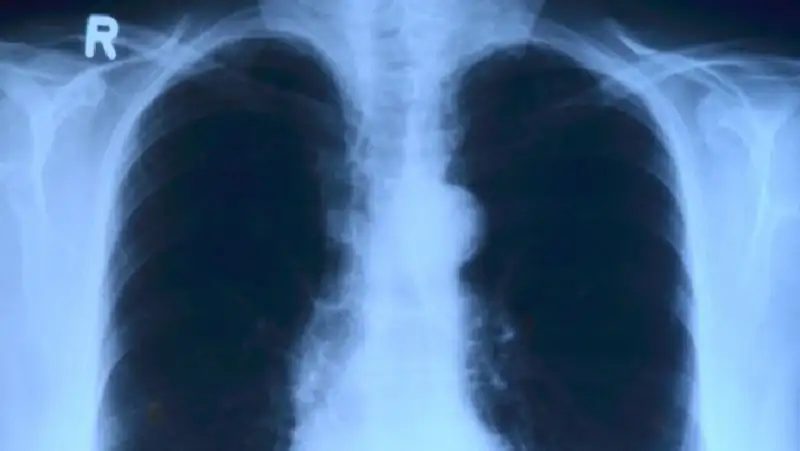

Скрининговые обследования – это минимальный комплекс медицинских исследований, направленный на выявление заболеваний на ранних стадиях, а также выявление факторов риска, способствующих возникновению заболеваний. В скрининговых осмотрах предусмотрены лабораторно-диагностические исследования и консультация узких специалистов.

Какие болезни выявляют с помощью скринингов?

• Раннее выявление поведенческих факторов риска – мужчины и женщины в возрасте 30-70 лет.

• Раннее выявление артериальной гипертонии, ишемической болезни сердца и сахарного диабета – мужчины и женщины в возрасте 40-70 лет, не состоящие на динамическом наблюдении по данным диагнозам.

• Раннее выявление глаукомы – мужчины и женщины в возрасте 40-70 лет.

• Раннее выявление рака шейки матки – женщины в возрасте 30-70 лет.

• Раннее выявление рака молочной железы – женщины в возрасте 40-70 лет.

• Раннее выявление колоректального рака – мужчины и женщины в возрасте 50-70 лет.

• Раннее выявление вирусных гепатитов В и С.